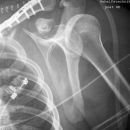

Schulterluxation